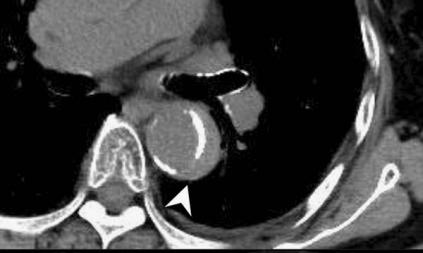

病例8

查到一篇文献,作者虽然用箭头标记了,并且是增强CT,但是鲁迅说:我大约肯定没有看出来,这是主动脉夹层!

图21